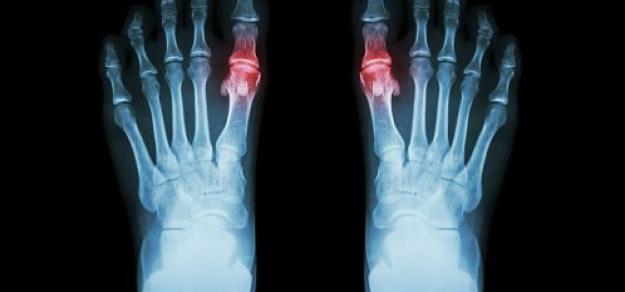

Diagnóstico y tratamiento de la hiperuricemia y la gota: revisión sistemática de las guías de práctica clínica y las declaraciones de consenso.

BMJ Open 2019Se necesitan mejoras en la calidad metodológica  de los documentos de orientación sobre gota e hiperuricemia. Falta evidencia para ciertas preguntas clínicas, a pesar de numerosos ensayos en este campo. Promover métodos de desarrollo de orientación estándar y sintetizar evidencia clínica de alta calidad son enfoques potenciales para reducir las inconsistencias de recomendación.

Hiperuricemia y tratamiento farmacológico de la gota

Butlletí d’informació terapèutica BIT. Vol. 30, núm. 2, 2019CatSalut, 10 de mayo de 2019Este Boletín revisa los tratamientos farmacológicos de los ataques agudos de gota y de la hiperuricemia haciendo un posicionamiento de los fármacos disponibles. Finalmente, se abordan diferentes controversias relacionadas con el tratamiento como el manejo de la hiperuricemia asintomática o la retirada del alopurinol.